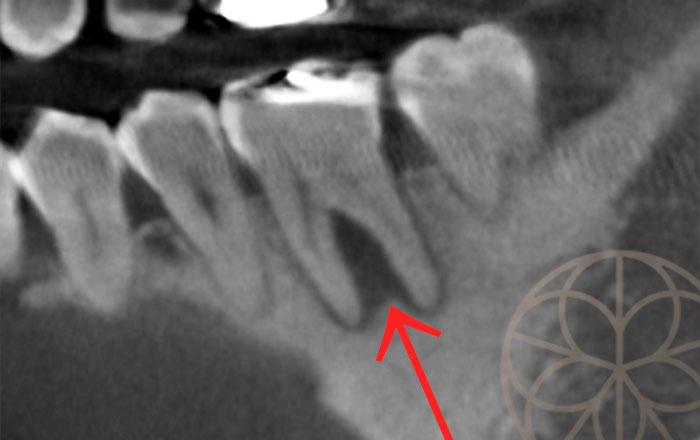

根の股の部分に大きな影(骨欠損部)が見られます。

同部をCTで確認し、0.1mm単位のスライスで確認すると、小さい影(病変)も見つけることができます。(赤矢印)この小さな影は、以前の治療をした部分から細菌感染をして根の中身が汚染しているため、根の先端の方に向かって細菌が移動して骨を溶かしています。

これは治療をしない限り治癒することはなく、長年の経過の中で大きくなっていきます。ある程度の大きさまで骨が溶けていくと、痛みが出てきます。